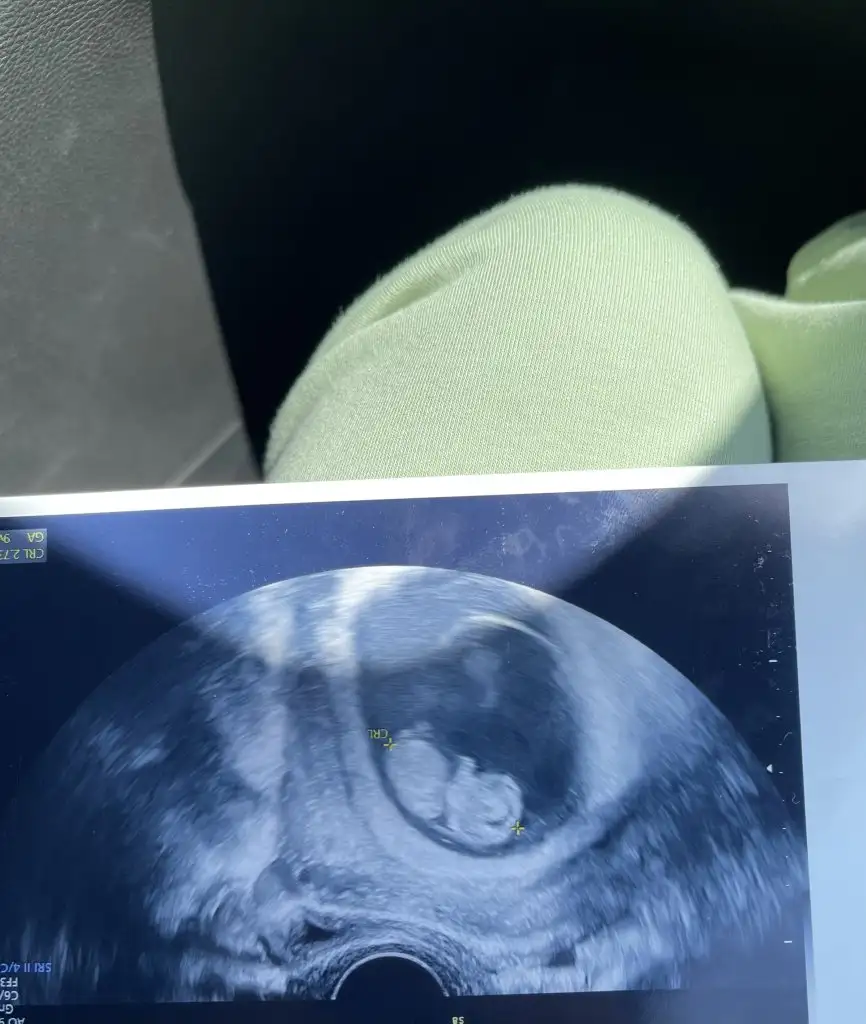

Kızlar bana da bakarmısınız rica etsem 🥲

8 hafta 3 günlük🥰❤️❤️❤️

• 1F6B46EC-91EA-48B5-8377-BF080C26134A.webp

1F6B46EC-91EA-48B5-8377-BF080C26134A.webp

22,3 KB · Görüntüleme: 71

• 9EFC7DA4-B21A-4931-826A-2EBC68104C51.webp

9EFC7DA4-B21A-4931-826A-2EBC68104C51.webp

16,5 KB · Görüntüleme: 59